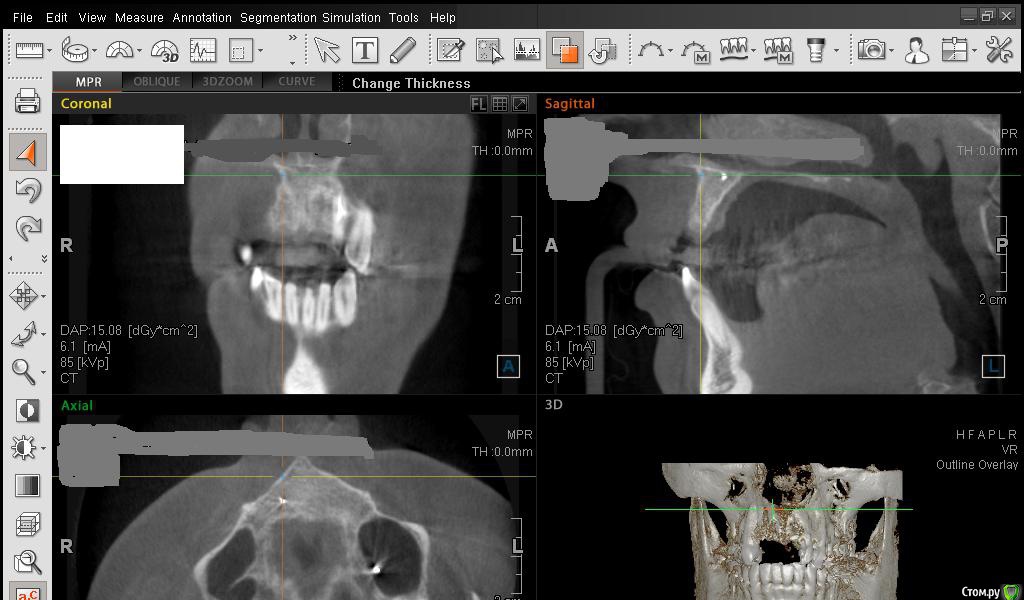

Сестричка Опубликовано 1 марта, 2015 Поделиться Опубликовано 1 марта, 2015 Добрый день! Ситауция такая-4 месяца назад удалено две верхние единички, двойка 7 месяцев назад была удалена. На всех зубах был хронический периодонтит, на одной единице был свищевой ход, гранулемы, единицы были резецированы. При удалении обеих единиц была одновременно проведена операция остеопластики (заполнили бон-боном, кальцием) в области разрежения кости и в места корней зубов. Вчера сделала КТ перед имплантацией, хирург пока ее не видел, но предупреждал, что возможно потребуется установка костного блока, также наращивание каким-то дорогим материалом десны. Выбирали систему имплантации Астра-тек, на первой консультации мне было популярно рассказано, что кость сама нарастает на эти импланты, по поводу остеопластики на втором этапе не было сказано ни слова. Такой вопрос-можно ли тут обойтись без костного материала, ведь кость уже вроде как наросла? Что скажете, уважаемые имплантологи? Прикрепляю снимок до удаления зубов и скрины свежего КТ. Спасибо! Ссылка на комментарий

SDC Опубликовано 1 марта, 2015 Поделиться Опубликовано 1 марта, 2015 Сестричка, в левом верхнем углу КТ есть инструмент, обозначен, как линейка.С помощью ее необходимо провести замеры альвеолярного отростка на КТ вертикально и горизонтально.Для увеличения объема десны используются различные трансплантаты, но пока лучше аутотрансплантата (собственной десны с неба) ничего нет. Ссылка на комментарий

Сестричка Опубликовано 2 марта, 2015 Автор Поделиться Опубликовано 2 марта, 2015 Сделала замеры, надеюсь правильно? Старалась измерить наиболее уязвимые и тонкие места. Изначально планировались размеры имплантов 3 мм на 11 мм длиной. Смогут ли они туда встать? Ссылка на комментарий